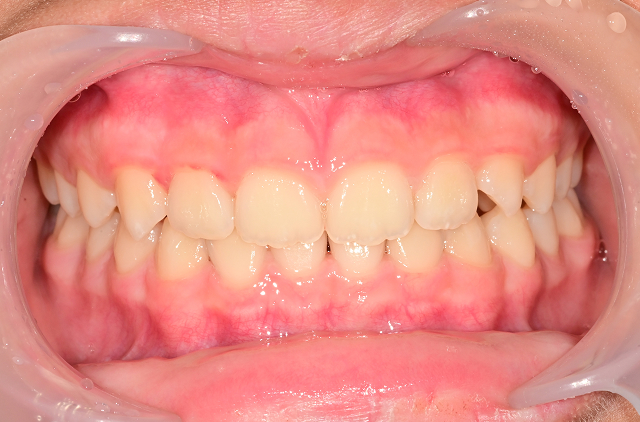

성장기 교정 방식

전통적인 장치 교정

턱 성장 방향을 조절하거나, 유치공간을 확보하는 장치를 사용합니다. (가철식 장치, 확장 장치, 헤드기어 등)

인비절라인 퍼스트 (Invisalign First)

- 장치가 투명하고 착용감이 좋아 아이들이 부담 없이 착용

- 디지털 스캔을 통해 성장 예측 기반으로 정밀한 설계

- 교정과 전문의가 성장 단계에 맞춰 장치 교체 시점 직접 관리